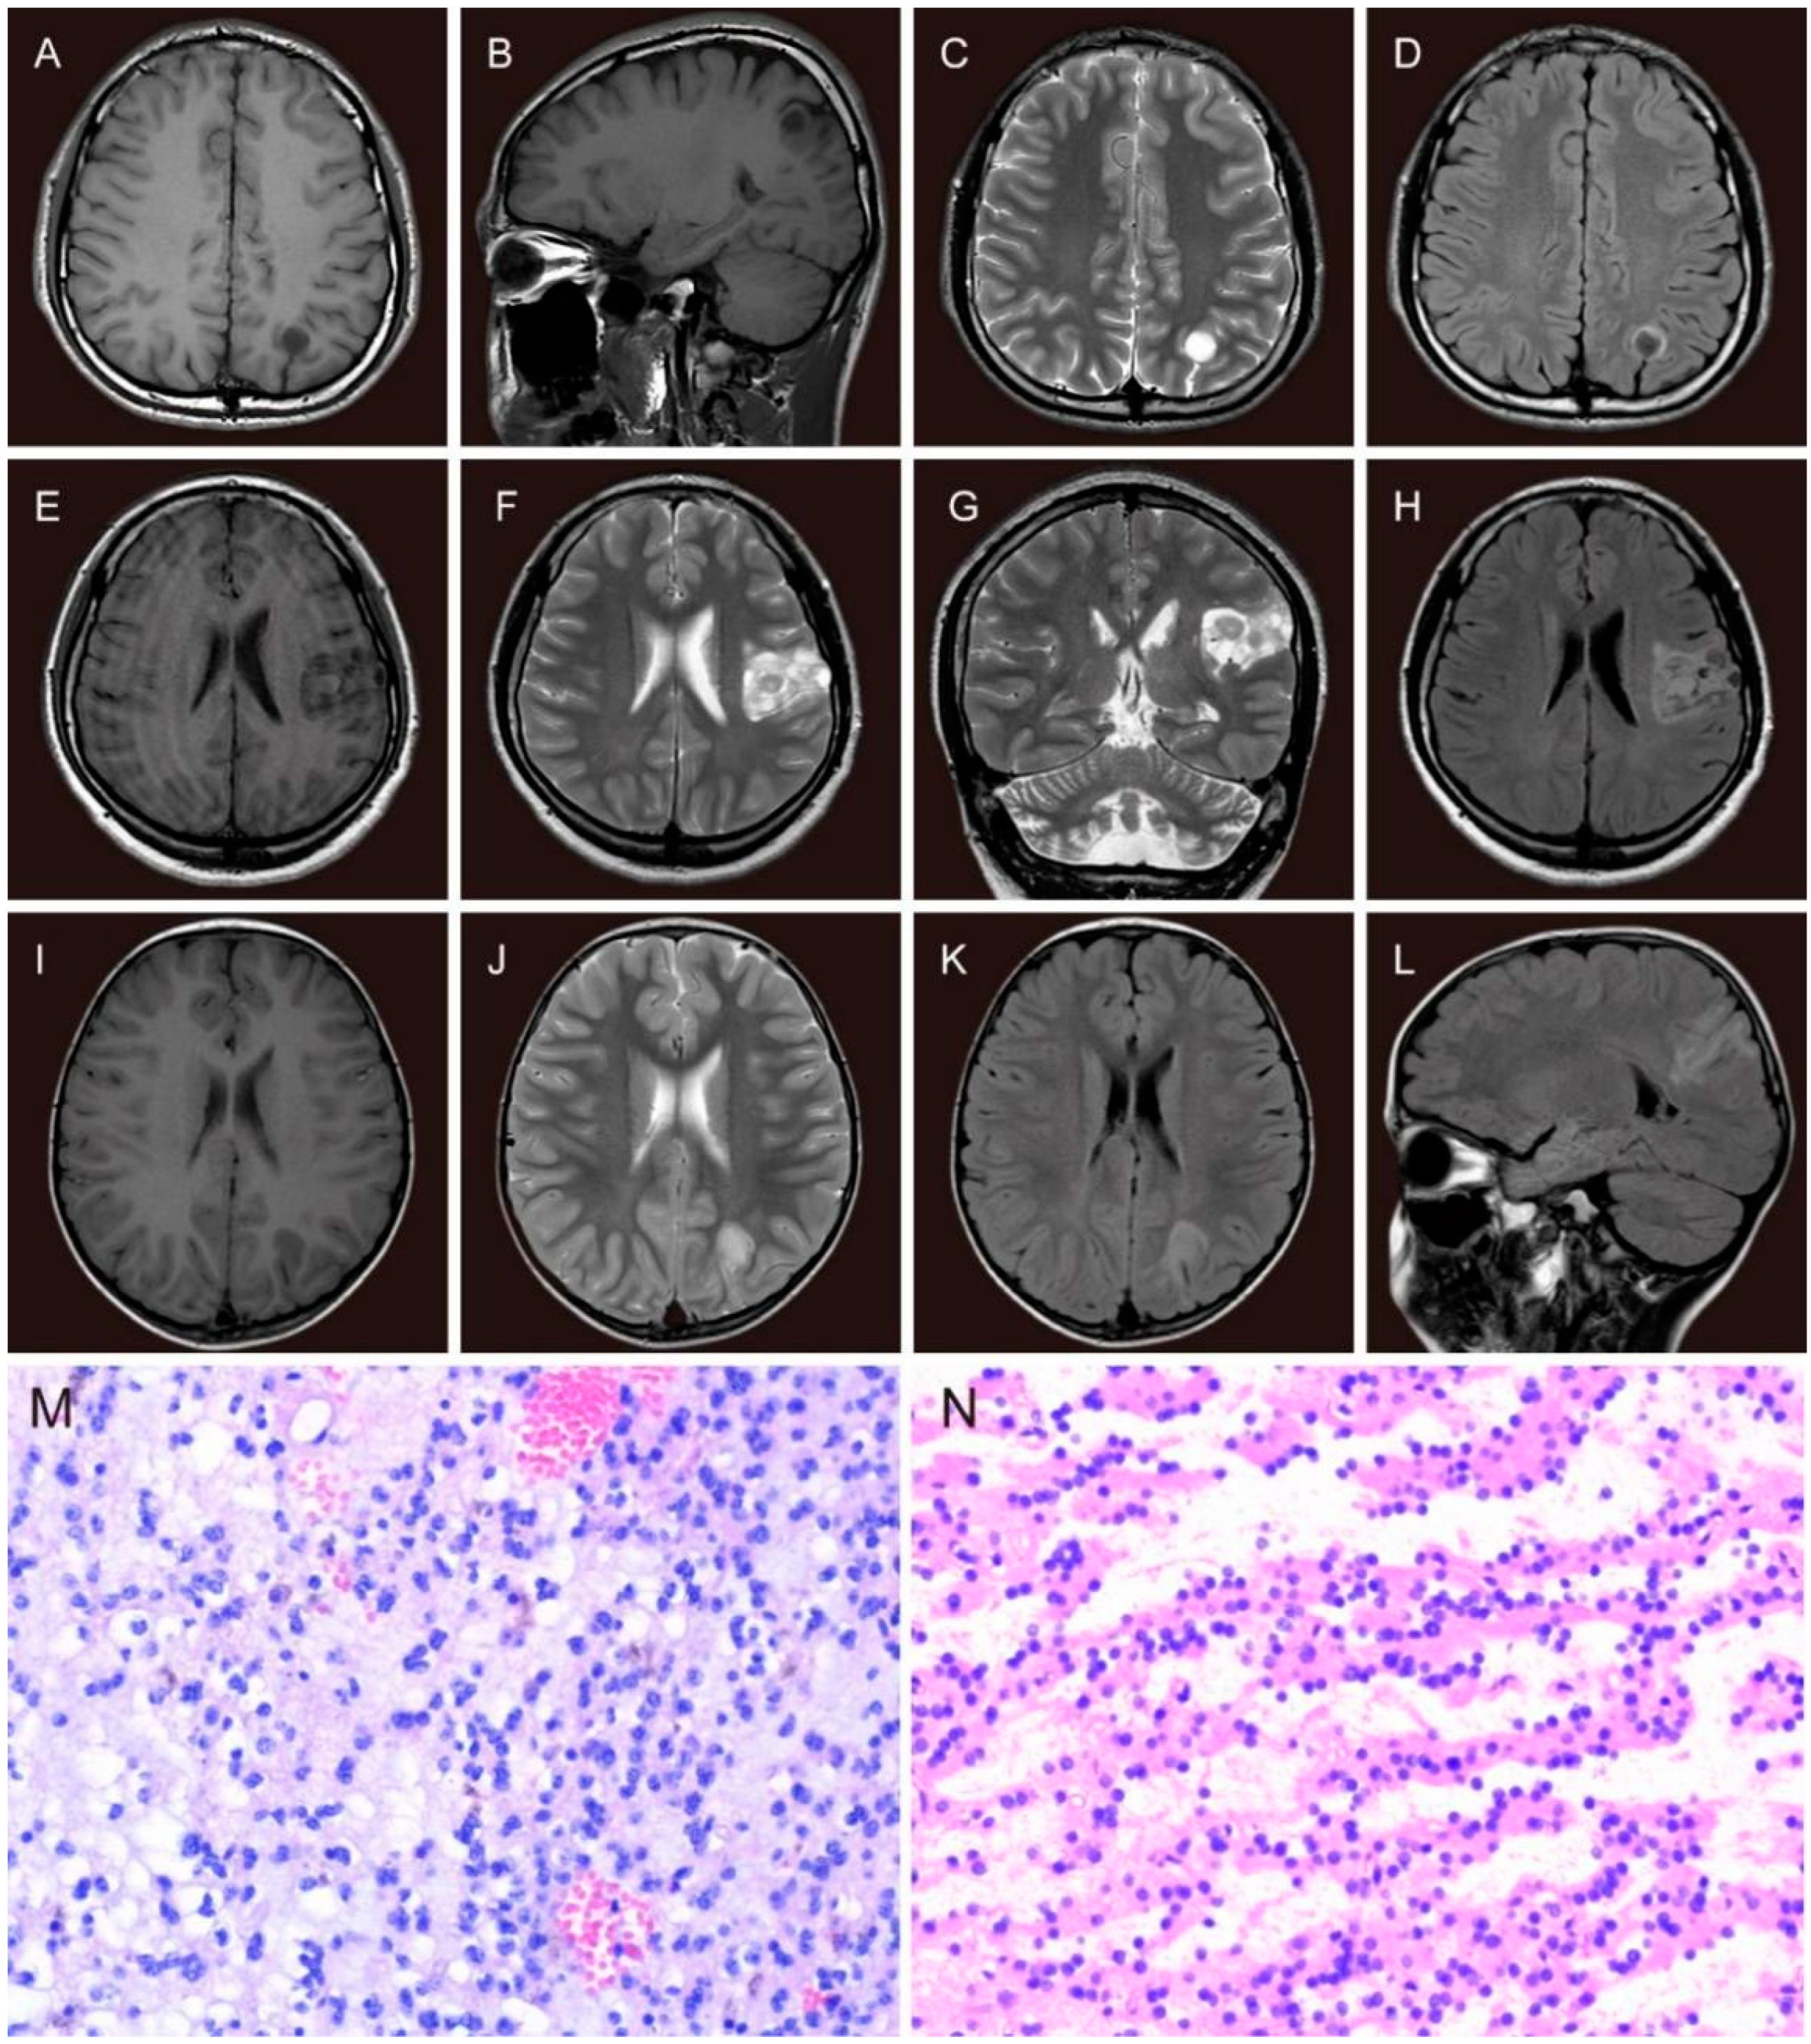

2.2. Presurgical Assessments

3.1. Demographic Characteristics

3.2. Clinical Characteristics